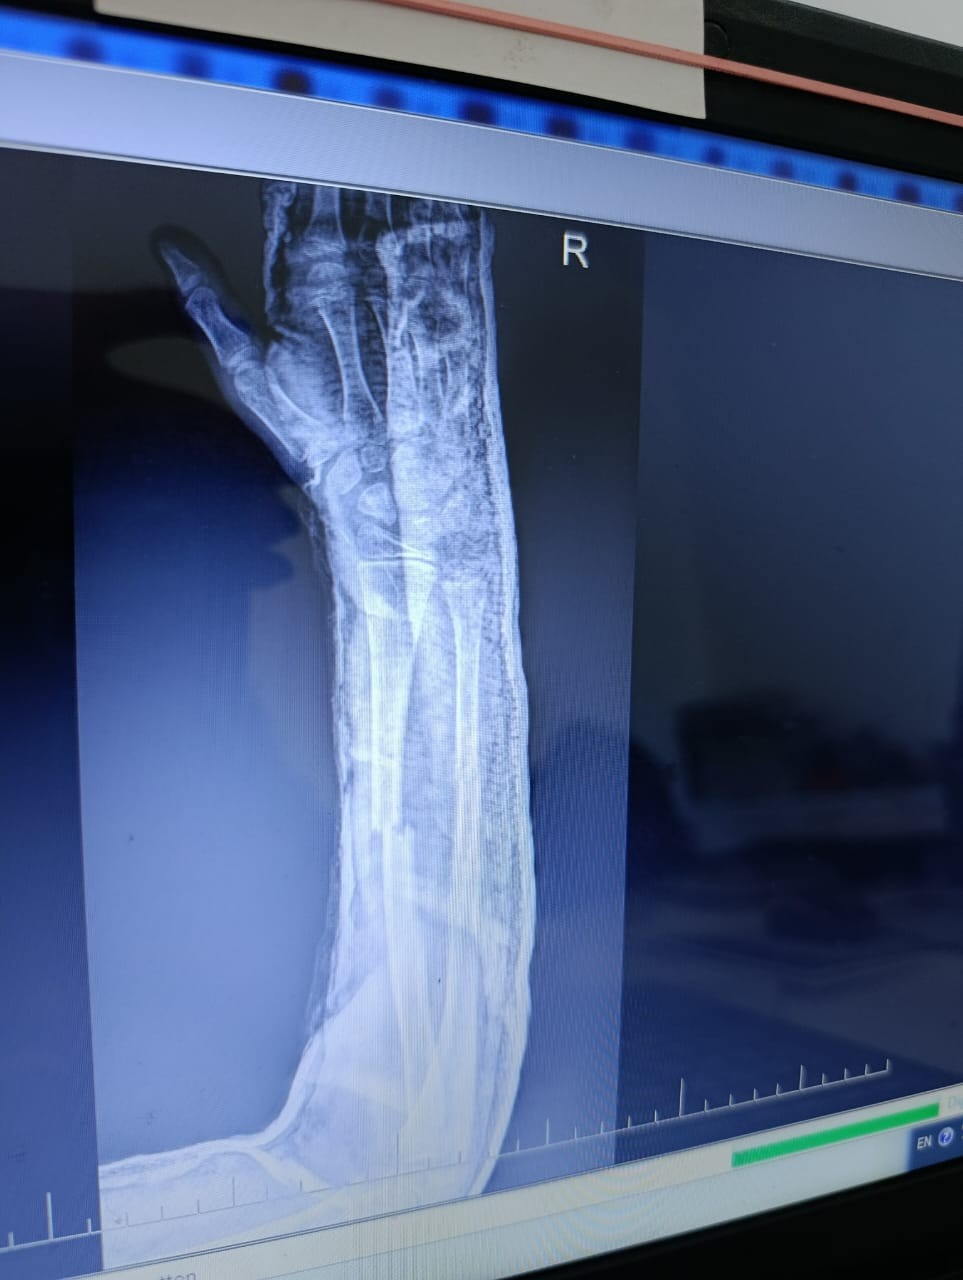

Здравствуйте, у сына, 10 лет, был перелом двух костей на правой руке. Одну кость вправили хорошо, другую на 50%. Врач говорит, что нет необходимости довправлять другую кость, но я переживаю и не понимаю как она может срастись. Сперва неделю ходил с лангетой, потом поставили гипс. Посмотрите пожалуйста снимки. Может ли кость нормально сростись или нужно настоять на операции, что бы вторую кость установили более ровно?